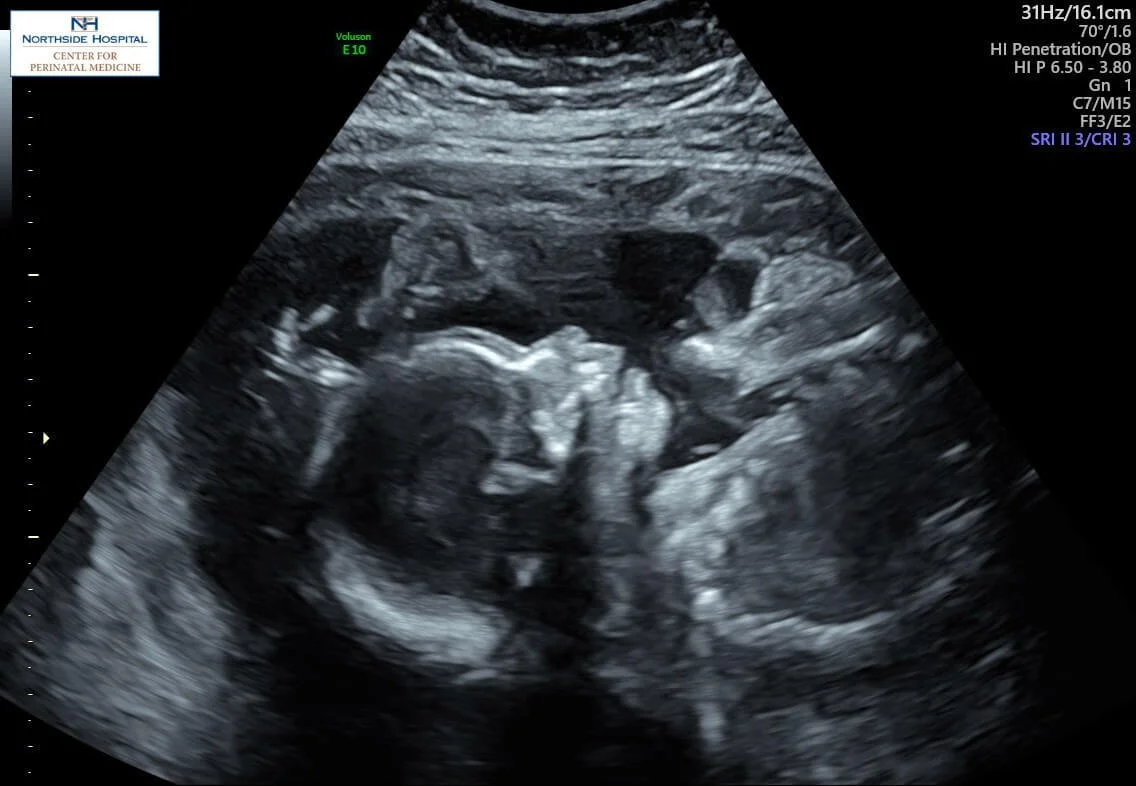

Then came the devastating news: during the ultrasound, the technician fell silent, her demeanor changing from friendly and professional to somber. I was told that my baby had either gastroschisis or omphalocele, a diagnosis that meant I would likely need a cesarean (this was not true). The rest of the appointment was a blur. I remember collapsing against the side of our car afterward, calling my mom in a panic, desperate for comfort and guidance.